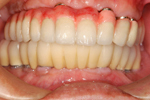

⑤ 上下とも治療の終わった状態。メインテナンスに入ります。

⑤ 治療後・前から見た状態

60才代 男性

総額:530万円(税別)

治療期間:2年

リスク副作用:経年的変化による補綴物の消耗。ブラッシング不足ですとインプラント周囲炎になります。